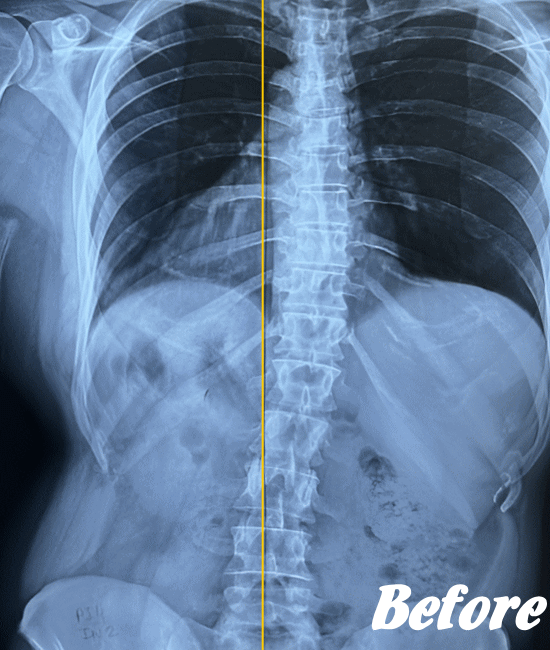

| 施術前(レントゲン) | 施術後(レントゲン) |

|---|---|

![]() |